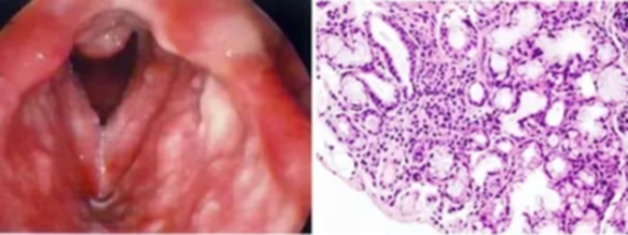

图为干燥综合征小唾液腺淋巴浸润的内镜下表现与组织病理学图像

消化系统改变:口干、吞噬困难(75%)、食管运动异常(36%)、萎缩性胃炎(钡餐或可有胃癌征象)、肝大(8%—23%,可有肝酶异常、肝脏淋巴细胞浸润),胰腺分泌功能下降(可有血浆胰蛋白酶、淀粉酶、脂肪酶升高)。